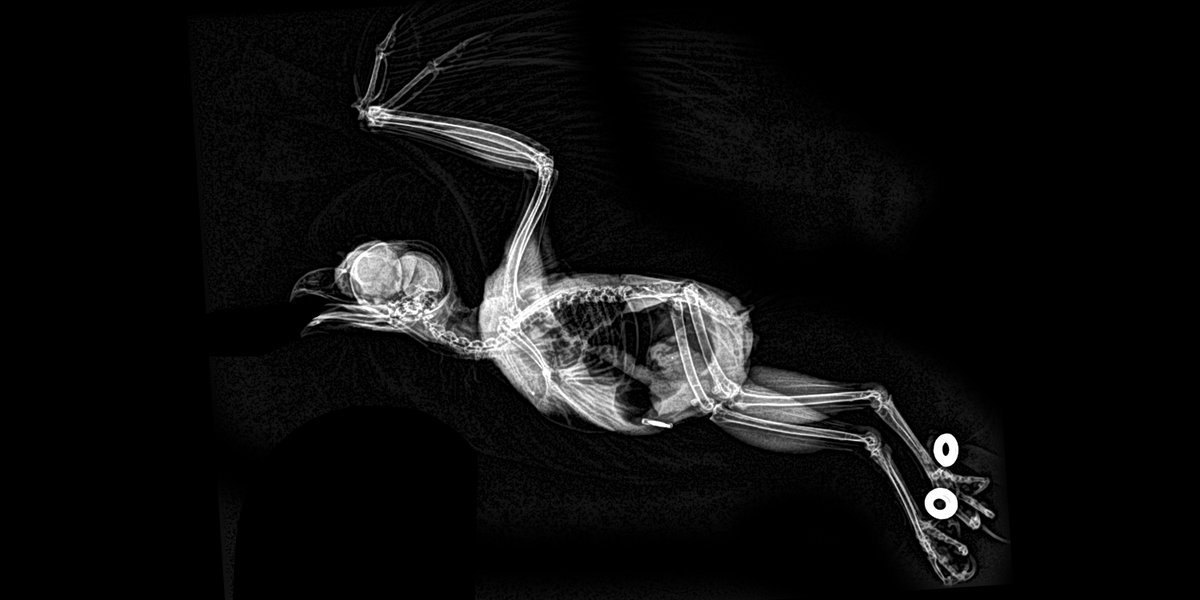

Patas de flamenco